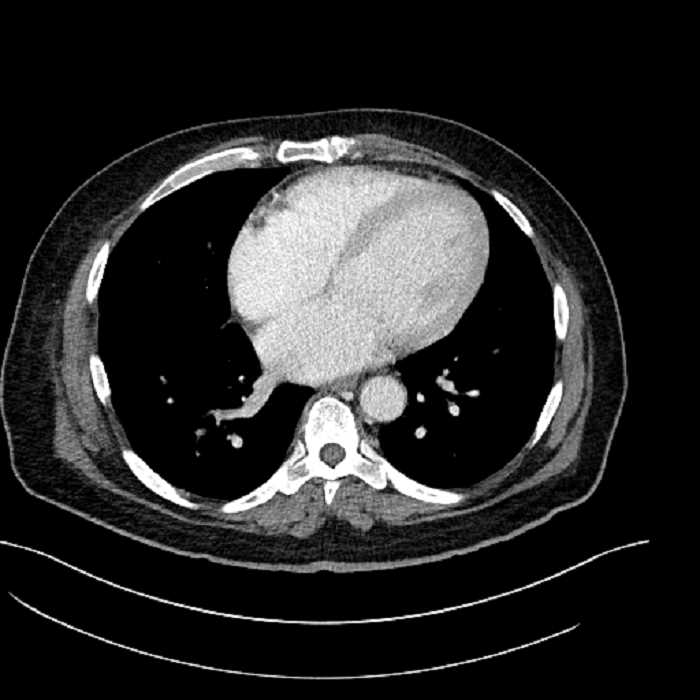

• Lower chest

• Mild cardiomegaly

• Mild dependent atelectasis

Acute sigmoid diverticulitis complicated by a small contained perforation and a large abscess in the right hepatic lobe. Additional small subcapsular abscesses along the anterior margin of the left hepatic lobe.